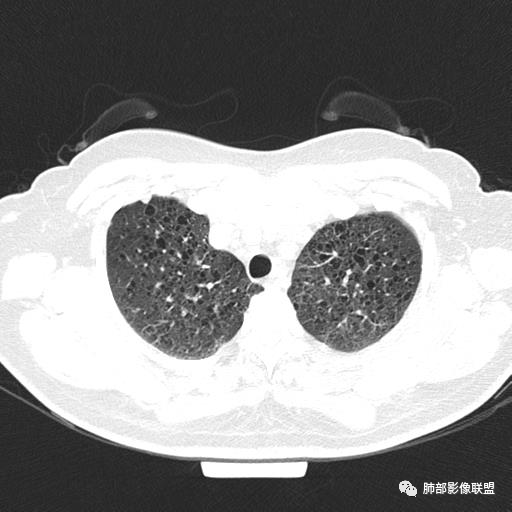

中年女性,不吸烟

双肺弥漫囊腔,累及肋膈角,囊腔形态相对规则单一。

符合LAM

CT平扫示双肺弥漫分布大小不等囊状薄壁透光区,无内、中、外带分布差异,间质稍示增厚。拟LAM

中年女性育龄期妇女,咳嗽气喘,无吸烟史,有苯吸入史。影像:双肺弥漫均匀小囊腔,无明显分布优势,囊腔形态欠规则,壁薄,部分囊腔边缘血管征,伴双肺弥漫磨玻璃影,无结节,考虑lam,鉴别苯中毒肺损伤,囊腔多有分布优势,小叶中心分布为主,形态规整等

女,46,活动性气喘1年。苯吸入史半年。胸部CT:两肺弥漫囊腔,上至肺尖,下至肋膈角,形态类似小囊腔。考虑:LAM,鉴别LIP,BHD,PLCH等。

双肺弥漫大小不一薄壁含气囊腔,囊间肺组织正常,正常肺背景,肺尖肺底受累;青年女性,气喘,支持LAM

双肺多发大小相近的囊状影,分布趋势趋于一致,中年女性,考虑LAM。部分囊内见血管及分隔影,小叶中心性肺气肿代排

CT表现:双肺弥漫大小不等的薄壁囊腔,囊壁<2mm,外形规则,血管影多位于囊腔周围,囊腔之间肺组织正常,随着疾病进展到晚期,囊腔变大、增多,不可胜数,囊腔可融合成较大的囊,与肺气肿相似,形成间质性肺纤维化。部分病例可出现结节影。